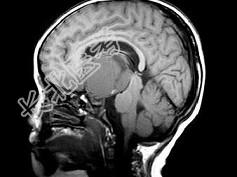

- 单项选择题女,8岁, 头痛、左侧肢体麻木十余天,根据所提供图像, 最可能的诊断是 ( )

A、表皮样囊肿

B、颅咽管瘤

C、垂体瘤

D、胶质瘤

E、蛛网膜囊肿